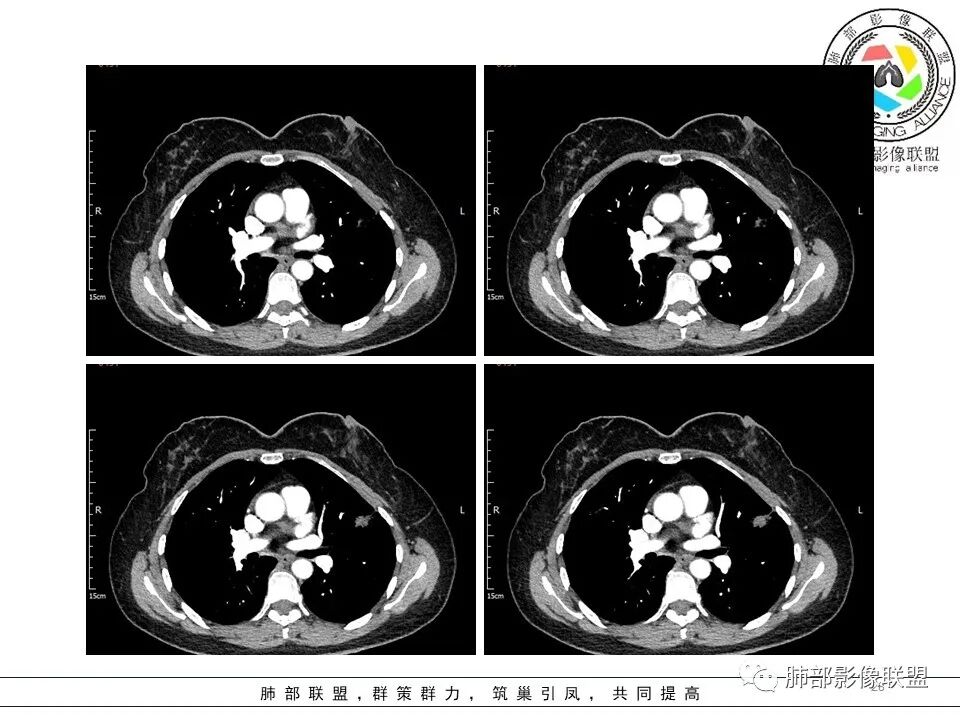

一.大结节影像特点:

左肺上叶胸膜下不规则结节影,分叶、粗短毛刺,胸膜牵拉等,像个“刺头”。

未见钙化,也未显示液化坏死或空洞。

与支气管相关,但取层未能显示支气管进入情况。

有几点应当引起我们高度重视:

1.病灶周围向几个方向膨出的边界清楚的磨玻璃影,这些磨玻璃影时隔几个月依然,几乎可以排除出血及一般的炎性改变。

2.病灶的胸膜牵拉线与其间病灶胸膜侧的磨玻璃边构成朝向胸壁的“月牙铲”结构,这种影像学表现某种程度上反映出病理学特征——病灶收缩+小叶间隔阻挡。

3.病灶实性密度区强化明显,这有助于我们区分一些其他类似病灶,如结核灶等!

4.邻近未见树芽征及卫星灶等。

结合临床,应当高度怀疑浸润性肺腺癌!